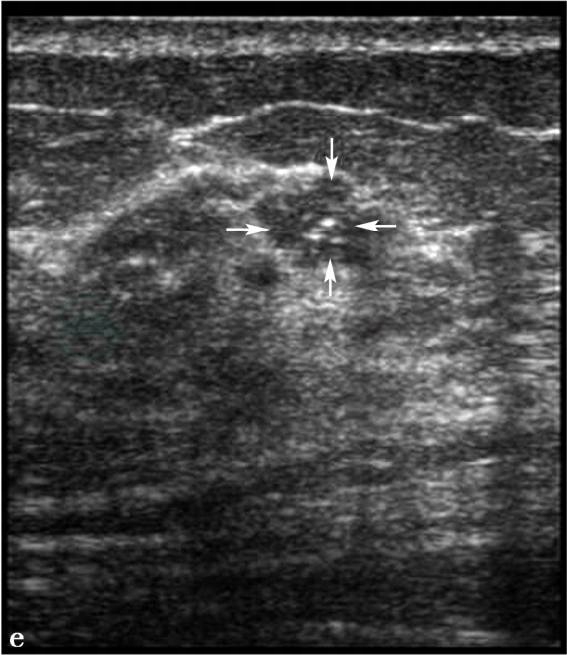

X线及超声检查。

图3 图3a,右乳X线头尾位。图3b,右乳X线内外斜位。图3c,右乳病变局部放大片。X线显示右乳呈脂肪型乳腺,右乳外上不规则分叶状肿物(图箭头所示),大小约1.8cm× 2.3cm,边缘呈蟹足状浸润,其内可见2枚点状钙化,皮下脂肪层清晰,皮肤及乳头正常。图3d,右乳病变二维超声图,超声显示右乳外上1.5cm×2.0cm低回声反射区,形状不规则,边界不清楚,边缘呈蟹足状浸润,内部回声不均匀,肿物后方可见声影。图3e,右腋下淋巴结二维超声图,右腋下可见1.3cm× 2.3cm肿大淋巴结,正常淋巴结门结构消失